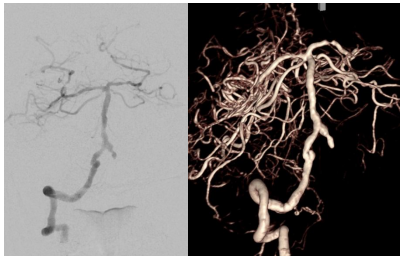

患者高先生,70岁,患有高血压病多年。2年前曾行冠状动脉搭桥术,平素规律服药。2个月前,他因左上肢突然麻木被送至清华大学垂杨柳医院急诊科就诊。头颅CT提示右侧顶叶少量蛛网膜下腔出血。后入住神经外科进一步诊治,全脑血管造影(DSA)结果显示:右侧椎动脉起始部重度狭窄约70%,左侧椎动脉颅内段闭塞;右侧椎动脉颅内段存在直径约3.5×2毫米的夹层动脉瘤;右侧颈内动脉颅外段存在重度狭窄,左侧颈内动脉通过前交通动脉代偿。

▲右侧颈内动脉颅外段重度狭窄,左侧颈内动脉代偿右侧颅内